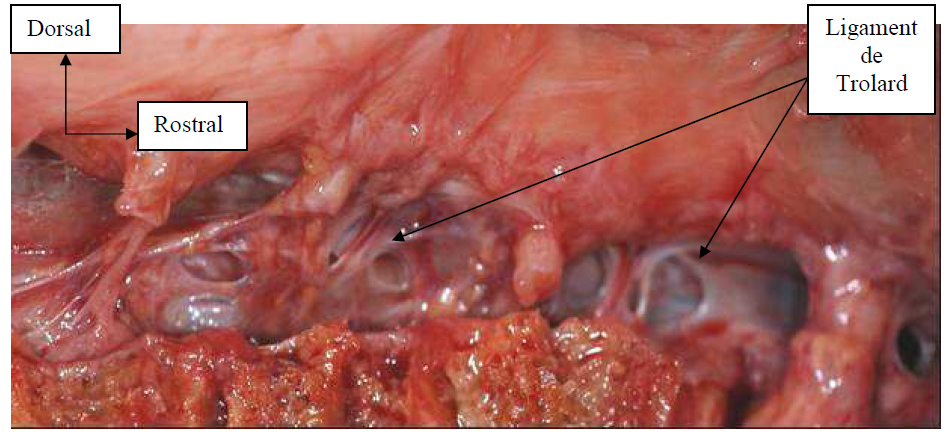

Photo INSERTIONS DE LA DURE-MERE SUR LE RACHIS Une anatomie redécouverte 8